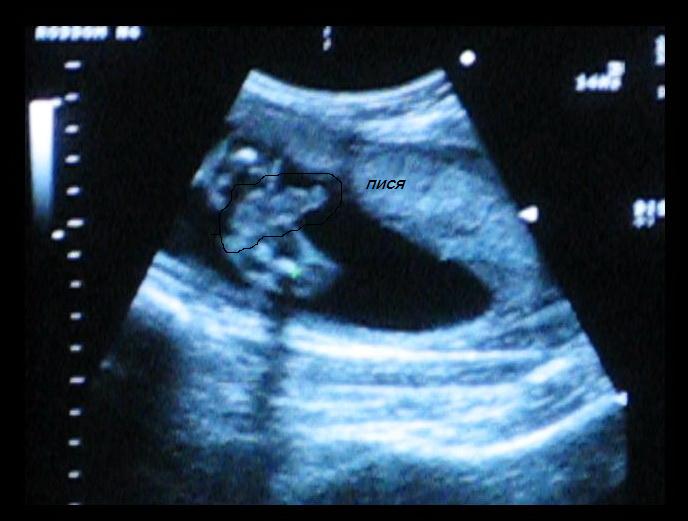

Скрин с видео сегодня сделала, что у нас мальчик, еще на 22 неделях на узи сказали

Нажмите на изображение для увеличения

Название: пися.JPG

Просмотров: 348

Размер:	39.0 Кб

ID:	2167

ПИСЯ - приколистка!!!!! Хотя, я тоже на след. приеме хочу врача фото сделать. А то он уже 3 раза мне фотки не давал, видать, фотать уже нечего.. а я еще хочу, хотя бы одну фотку... вот и думаю, мож тож попросить писю сфотать... (не МОЮ - малыша )!!